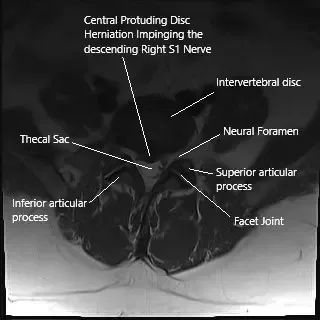

Axial section of the spine on MRI showing herniated intervertebral disc.

Diagnosis is typically clinical, based on a patient’s history and physical examination. Imaging tests like MRI are crucial for identifying disc herniations, degenerative changes, and other structural abnormalities in the lumbar spine. MRI scans in sagittal and axial views provide detailed images of the disc space, nerve roots, and the surrounding structures, helping guide treatment decisions.

The most common cause of sciatica is a herniated lumbar disc, where the disc material presses on the nerve root. Other causes include degenerative changes such as facet arthritis, spinal stenosis, or osteophyte formation. Sciatica can also result from synovial cysts or trauma. These conditions irritate or compress the nerve roots, leading to inflammation, ischemia, and pain.